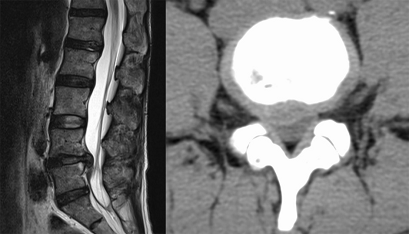

近日,一名48岁的中年患者张生(化名)因长期腰痛来我科问诊,经过我科医生团队的仔细检查发现,该患者为严重的腰椎间盘突出症,椎间盘长期压迫神经,导致张生久坐、久站都会出现难以忍受的疼痛感,就连日常走路都需要扶着腰,无法正常工作和生活。

这种情况下药物治疗对于张生来说已经无济于事,手术是唯一的办法;但是,张生觉得自己还年轻,做完手术不能影响日后生活,他的要求是希望我们能为他解除疼痛,但是要快速恢复,不要留下很大的疤痕影响面美观。于是,我们想到了脊柱内镜完全符合张生的需求,在经过2小时的手术后,压迫神经的椎间盘被完全摘除,张生仅留下2厘米的伤口。

脊柱内镜手术过程就是医生在放大镜的指引下通过小孔把椎间盘摘除,但是这种技术非常依赖手术医生的经验和技术水平,稍不注意就会摘除不彻底或者伤及神经、血管。我科自2016年在自贡市率先开展该项技术,手术量突破千例,积累了丰富的手术经验,技术水平已经非常成熟,有椎间盘突出严重的患者朋友前来咨询!